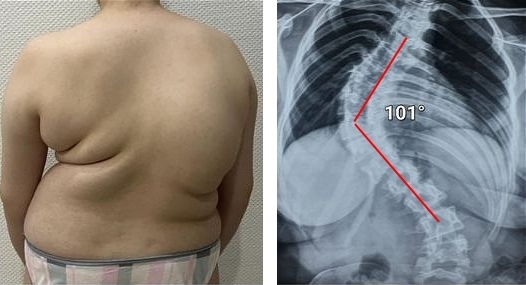

— Apakah Anda benar-benar berpikir bahwa pijat atau analgesik dapat mencegah kerusakan sendi dan tulang rawan? Itu adalah kesalahpahaman besar. Obat-obatan dari apotek tidak dapat meregenerasi jaringan, sementara bahan kimia yang terkandung di dalamnya justru merusak hati dan ginjal seiring waktu. Tubuh tidak dapat selamanya menanggung beban racun ini, dan alih-alih menyelesaikan masalah, Anda justru meracuni diri sendiri! Hal ini terutama berlaku untuk tulang belakang. Semua sendi mengalami keausan, tetapi pada tulang belakang, kurangnya ujung saraf dapat menyembunyikan perubahan yang berbahaya. Kompresi saraf skiatik akibat hernia adalah proses yang menyakitkan, awalnya menyebabkan nyeri ringan di punggung bawah, lalu menjalar ke kaki, menyebabkan kesemutan, mati rasa, dan akhirnya hilangnya fungsi kaki sepenuhnya. Kerusakan yang terus berkembang akan menyebabkan kelumpuhan pada bagian bawah tubuh, dan mengembalikan kendali atasnya menjadi hampir tidak mungkin. Lihat gambar ini. Ini adalah kondisi tulang belakang seseorang yang baru berusia 44 tahun, tetapi tampak seperti lansia. Dulu, kerusakan seperti ini hanya terjadi setelah usia 60 tahun, tetapi sekarang hal ini menjadi umum bagi mereka yang baru saja melewati usia 40 tahun. Kerusakan ini akan terus berkembang seiring bertambahnya usia, dan mengabaikannya berarti menempatkan diri dalam risiko kelumpuhan total!

Tulang belakang pasien berusia 44 tahun: semuanya dimulai dengan nyeri ringan, tetapi hanya dalam satu minggu muncul hernia, dan dalam dua minggu terjadi pergeseran tulang belakang, tekanan pada saraf, dan akhirnya—kursi roda.

Wanita, 52 tahun. Pergeseran parah dan deformasi cakram tulang belakang dengan kompresi saraf serta kerusakan sumsum tulang belakang.

"Punggung bungkuk janda" — deformasi tulang belakang yang menyebabkan nyeri tak tertahankan yang semakin memburuk setiap hari.